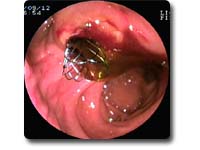

ERCP及EST技术

ERCP是将十二指肠镜经口插入十二指肠,寻找十二指肠乳头,再经活检通道置入造影导管并插入乳头,在X线透视下注入造影剂显示胆管、胰管的形态及异常变化。ERCP是胆道和胰腺疾病最为有效的诊断技术之一,也是胆胰疾病内镜下介入治疗的基础。包括:急性化脓性胆管炎、急性胆源性胰腺炎、胆总管结石、胆道蛔虫、梗阻性黄疸术前引流、胆瘘、胰瘘、慢性胰腺炎等。